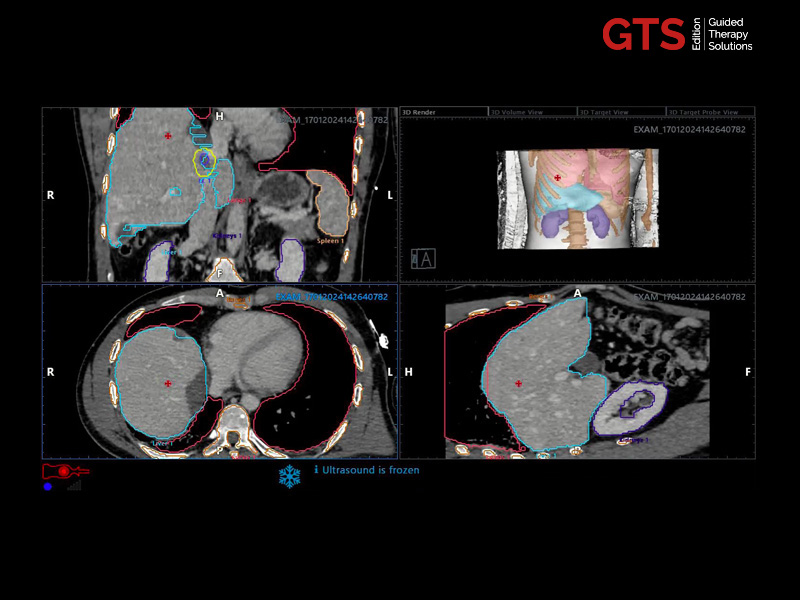

The targeted and systematic biopsy samples will be automatically saved in a 3D prostate rendering volume, a complete and clear report is automatically completed and attached to each procedure.

Transperineal & transrectal targeted biopsy (based on a 3D prostate reconstruction & sample mapping) - UroFusion report - Automatically generated

The steppers are also compatible with UroFusion, allowing for full targeted treatment by using:

- the biopsy fusion procedure prior to treatment, which combines the core position and histopathology of the target areas to be treated (recorded on the report with sample mapping and 3D reconstruction)

- and/or mpMRI guidance, which identifies the suspicious areas.